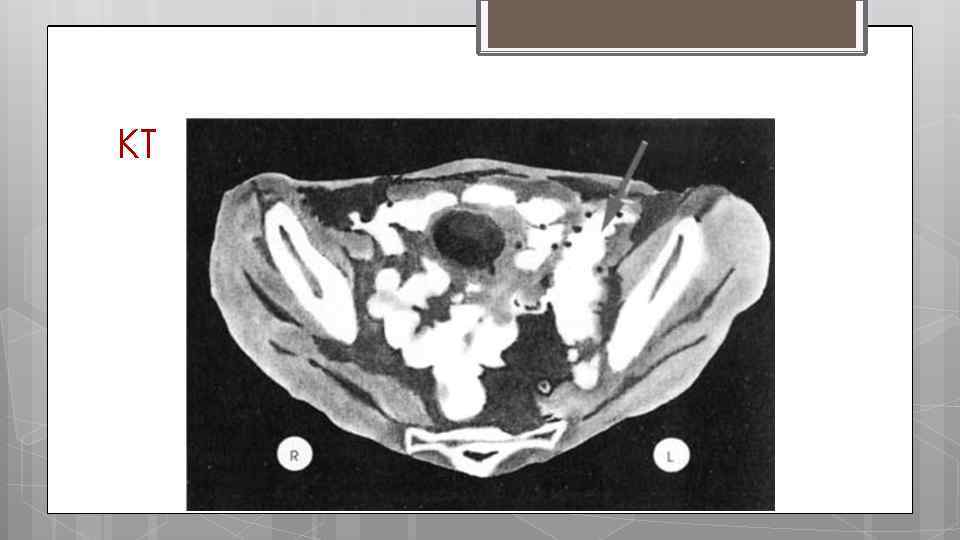

Диагностика дивертикулёза толстой кишки. Ирригография, скопия Колоноскопия Общий анализ крови Диагноз м. б. подтверждён с помощью: o КТ o УЗИ

КТ